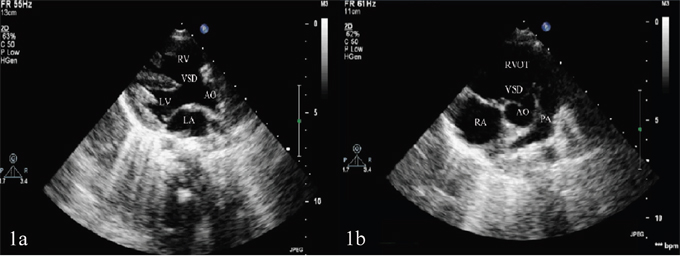

All the eight TOF children manifested cyanosis and rough systolic-ejection murmurs at the left sternal border between the second and fourth ribs. Echocardiography showed right ventricular enlargement, right ventricular anterior wall thickening, right ventricular outflow tract and pulmonary artery stenosis, ventricular septal defect and aortic overriding (Figure 1). The echocardiographic results of eight TOF children in the right ventricle, right ventricular anterior wall, right ventricular outflow tract, main pulmonary artery, left pulmonary artery, right pulmonary artery, ventricular septal defect and left ventricular ejection fraction (Table 1). The eight TOF children displayed no other malformations, and their parents showed no abnormalities.

Figure 1: (A) Ventricular septal defect and aortic overriding shown in the left ventricular long-axis view of transthoracic echocardiography. (B) Pulmonary artery stenosis shown in the aorta short-axis view of transthoracic echocardiography.

LA: left atrium; LV: left ventricle; AO: aorta; VSD: ventricular septal defect; RA: right atrium; RV: right ventricle; PA: pulmonary artery; RVOT: right ventricular outflow tract.